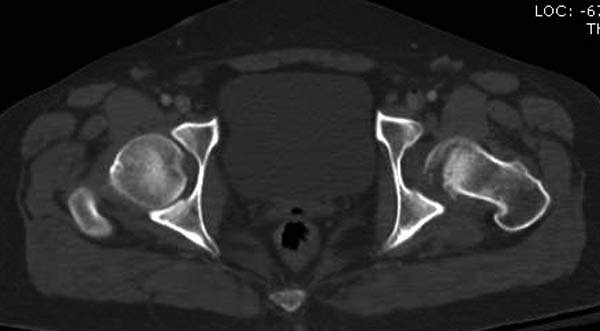

Женщина 28 лет, политравма.

По протоколу обследования больных с травмой сделаны все исследования и выставлен диагноз: разрыв печени и селезенки; множественные переломы ребер и лицевого черепа; стабильный перелом позвоночника, переломо-вывих головки левого бедра, перелом диафиза правого бедра, переломо-вывих правого тарана.

Вложение не в текстовом формате было извлечено&hellip;

Имя     : 7CT2.JPG

Тип     : image/jpg

Размер  : 21412 байтов

Описание: отсутствует

Url     : http://weborto.net:8080/pipermail/ortho/attachments/20120618/4c283bf6/attachment-0021.jpg